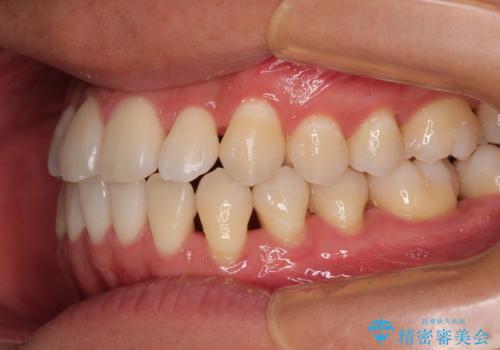

- 上下前歯部のデコボコを主訴として来院された患者様です。

上顎の歯列弓が下顎に対して狭いため、臼歯のかみ合わせがが咬頭対咬頭の状態です。

歯列弓の拡大により約1年で矯正治療を終えることができました。

正中も合わせることができ、非常にきれいに仕上がりました。